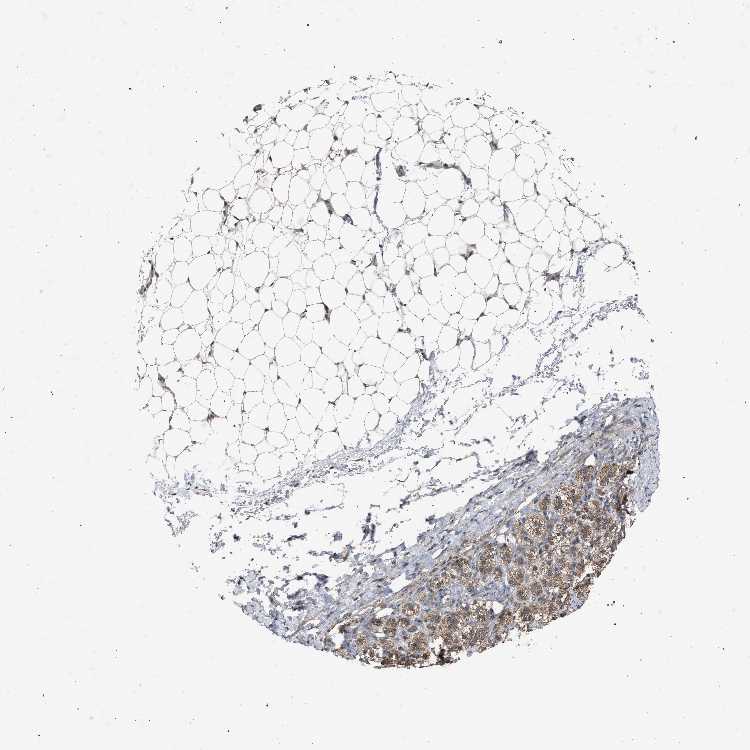

ADRENAL GLAND - Antibody stainingi

Antibody staining in the annotated cell types in the current human tissue is reported as not detected, low, medium, or high, based on conventional immunohistochemistry profiling in selected tissues. This score is based on the combination of the staining intensity and fraction of stained cells.

Each image is clickable and will lead to virtual microscopy that enables deeper exploration of all samples and also displays staining intensity scores, fraction scores and subcellular localization as well as patient and tissue information for each sample.

Antibody HPA021302Antibody HPA021311Antibody HPA021479

Glandular cells MediumMediumMedium